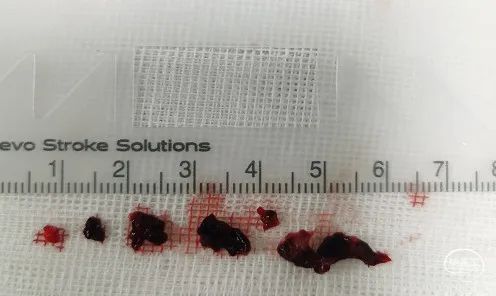

持续接触抽吸90秒后,回撤抽吸导管;抽吸导管进入长鞘之前,开启长鞘负压抽吸;发现血栓卡在长鞘头端、抽吸导管撤出长鞘后发现长鞘内无回血(白色短箭头)。20ml注射器连接长鞘、持续负压抽吸下撤出长鞘;长鞘在进入8F穿刺鞘前,开启穿刺鞘负压抽吸(白色长箭头)。最终成功将血栓从长鞘内抽吸出。

抽吸出的质韧血栓。